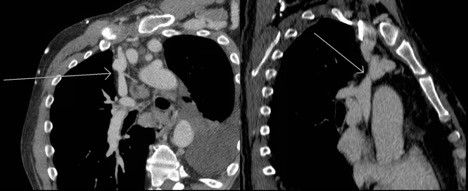

Figure 1. Oblique reformatted chest CT demonstrating nonocclusive stenosis of the distal portion of the SVC. Note the synechiae or "web" within the innominate vein.

Given his chronic immunosuppression, he was admitted by internal medicine for initiation of intravenous (IV) antibiotics. Thoracic surgery, transplant infectious disease, and nephrology were consulted following admission. He underwent an echocardiogram, which did not demonstrate congestive heart failure. A computed tomography (CT) scan demonstrated right internal jugular occlusion, superior vena cava (SVC) stenosis, prominent thoracic venous collaterals, and cervical and mediastinal lymphadenopathy (Figures 1 and 2). His pleural fluid cytology and cultures were negative, but testing indicated the presence of chylomicrons and his triglyceride level was 1154 mg/dL, which was consistent with a chylothorax.